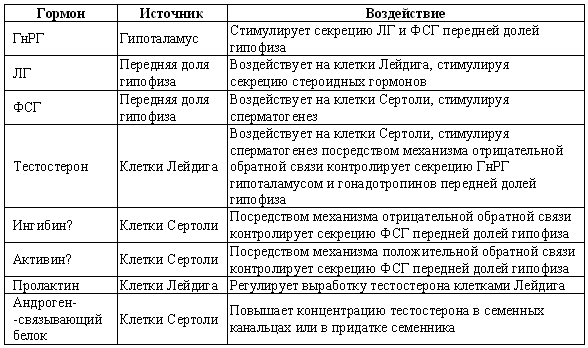

Стадия проэструса характеризуется развитием фолликулов под влиянием гонадотропных гормонов — лютеинизирующего (ЛГ) и фолликулостимулирующего (ФСГ), выделяемых передней долей гипофиза. Секреция этих гормонов регулируется гипоталамическим гонадотропинрилизинг гормоном (ГнРГ). У собак, так же, как и у других животных, вслед за пиком концентрации эстрадиола возникает (спустя сутки или чуть больше) пик концентрации ЛГ (фиг. 1.1). Таким образом, выброс ЛГ происходит всегда автоматически вслед за повышением активности фолликулов, вырабатывающих эстрадиол, и поскольку овуляция следует за возникающим без внешней стимуляции пиком концентрации ЛГ, ее называют спонтанной. Описанная ситуация разительно отличается от картины, которую можно наблюдать у кошек, для которых характерна индуцированная овуляция: у них выброс ЛГ и овуляция происходят вслед за коитусом. Насколько можно судить, у таких животных эстрадиол не способствует активации секреции ЛГ.

Повышение уровня ФСГ необходимо для стимуляции развития фолликулов и секреции эстрадиола, однако концентрация ФСГ в крови не достигает столь высоких значений, какие наблюдаются при пике ЛГ; это объясняют действием ингибина — белка, секретируемого фолликулами, который избирательно подавляет секрецию ФСГ Тем не менее ФСГ играет важную роль в созревании фолликулов и подготовке их к трансформации в желтые тела после овуляции. Начало трансформации фолликулярных клеток рассматривают как ключевой момент всего цикла, поскольку оно сопровождается преовуляторным повышением секреции прогестерона (фиг. 1.1), которое, по-видимому, играет ведущую роль в пусковом механизме овуляции и подтверждении эструса. Наблюдаемый у собак преовуляторный рост концентрации прогестерона нетипичен для других домашних животных, в частности для жвачных, у которых наступление эструса и овуляции происходит на фоне минимального уровня прогестерона. Однако преовуляторная концентрация прогестерона у собак все же относительно низка, и следует помнить, что назначение высоких доз прогестагенов в период проэструса вызывает отсрочку эструса и овуляции.